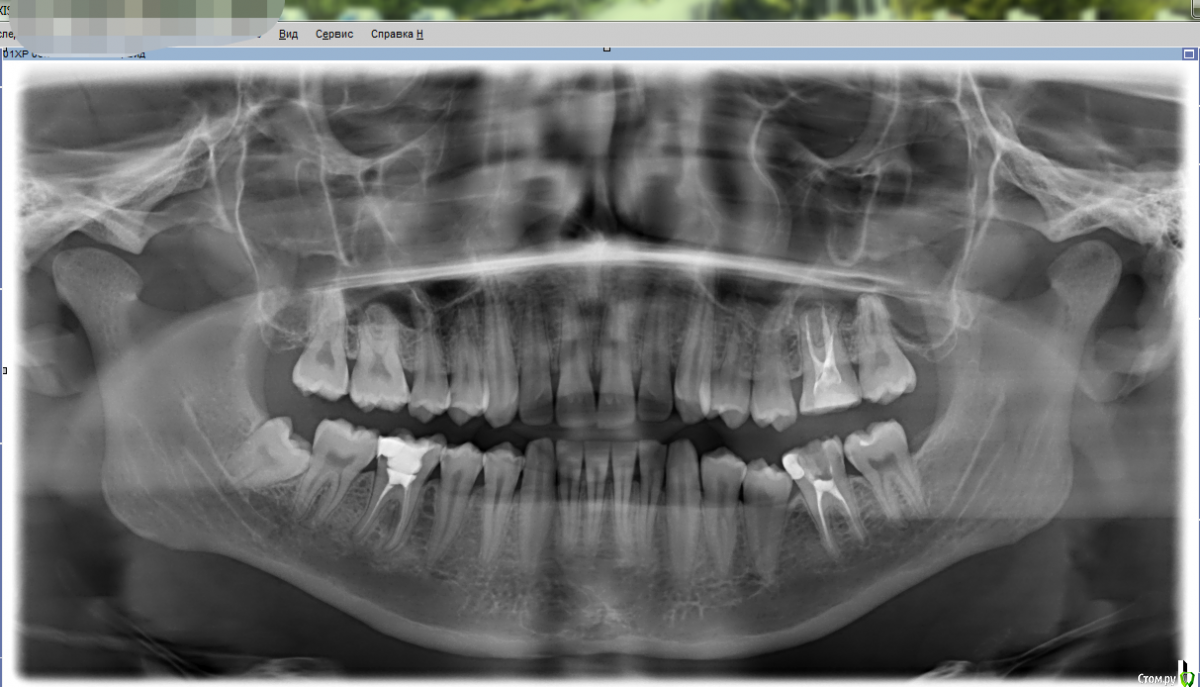

Усман Опубликовано 25 марта, 2019 Поделиться Опубликовано 25 марта, 2019 (изменено) Добрый день!Мне сказали, что у меня периодонтит на 26,36,46 зубах, выяснилось случайно после рентгеновского обследования. Пока ничего не беспокоит, в связи с этим хочу спросить:1) Насколько всё серьёзно? Можно ли пока не лечить, ибо лечение недёшевое, и чем черевато откладывание лечения в моём случае?2) Посмотрите пожалуйста остальные зубы тоже, т.к в другой клинике мне сказали. Что есть периодонтиты и под здоровыми (непломбированными) зубами, и что это, видимо, особенность моего организма. По какой причине инфекция развивается под здоровыми зубами? И что нужно делать, чтобы этого избежать в будущем? Действительно ли это особенность организма?3) Есть ли какие-либо народные методы лечения периодонтита, аля полоскания чем-нибудь и.т.д.?4)Также посмотрите пожалуйста все ли каналы запломбированы в 26 зубе?Прикрепил ссылку на снимок 36 зуба за октябрь 2017-гоИ снимок всей челюсти, сделанный в начале марта 2019-го5)Был ли периодонтит 36-го зуба в 2017 ? Каковы изменения за 1,5 года?https://yadi.sk/i/iUB0i3COcZfyqwЗаранее благодарен! Изменено 25 марта, 2019 пользователем Усман Ссылка на комментарий

red_butler Опубликовано 26 марта, 2019 Поделиться Опубликовано 26 марта, 2019 Насколько всё серьёзно? серьезно Можно ли пока не лечить можно, но не нужно и чем черевато откладывание лечения в моём случае? потерей зубов Что есть периодонтиты и под здоровыми (непломбированными) зубами, и что это, видимо, особенность моего организма. не вижу других периодонтитов Есть ли какие-либо народные методы лечения периодонтита, аля полоскания чем-нибудь и.т.д.? ха ха Также посмотрите пожалуйста все ли каналы запломбированы в 26 зубе? требуется повторное лечение каналов 2 Ссылка на комментарий

DmitrySH Опубликовано 27 марта, 2019 Поделиться Опубликовано 27 марта, 2019 Благодарю!А какой из зубов с периодонититом самый плачевный? Какой лечить первым ? 26 зуб, обычно не будет болеть, но легко создаст хронический гайморит Ссылка на комментарий